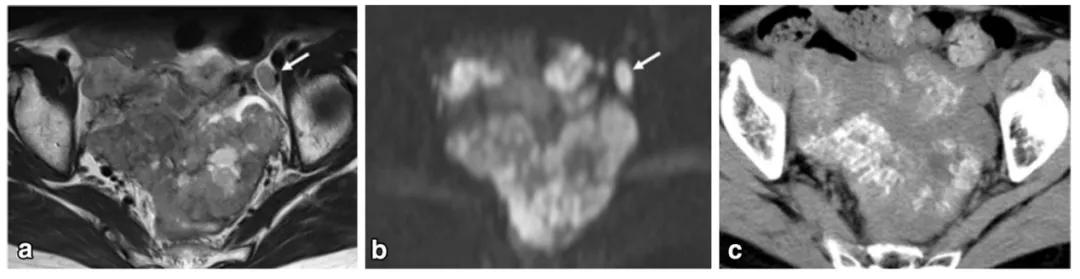

女,50 岁,卵巢甲状腺肿。左卵巢肿物,T2WI 呈不均匀稍高信号(图 a),增强扫描早期明显强化(图 b),CT 扫描显示囊内成份密度稍高(图 c)。

卵巢甲状腺肿是一种高分化单胚层畸胎瘤,较为罕见,发病年龄高峰为育龄期妇女,约 5%~8% 的卵巢甲状腺肿患者表现为甲状腺功能亢进症,肿瘤切除后甲亢症状可随之消失。卵巢甲状腺肿是以单侧附件发生的囊性或囊性成分为主的囊实性占位,单纯实性或实性为主的肿块较少见。囊腔信号各异及 T2WI 低信号被认为是该病最具鲜明的 MR 特征。病灶内出血或甲状腺滤泡内蛋白胶质成分可致 T1WI 信号增高,T2WI 内低信号影,可考虑为甲状腺滤泡内胶冻样物质,DWI 扫描呈异常高信号,由于胶冻样物质氢质子含量少,水分子扩散受限。囊壁和间隔一般较厚,但囊壁光滑,囊壁和间隔可见线样及环形钙化,增强扫描实性成分明显强化,尤其是呈甲状腺策划样异常显著的强化较具特征性。